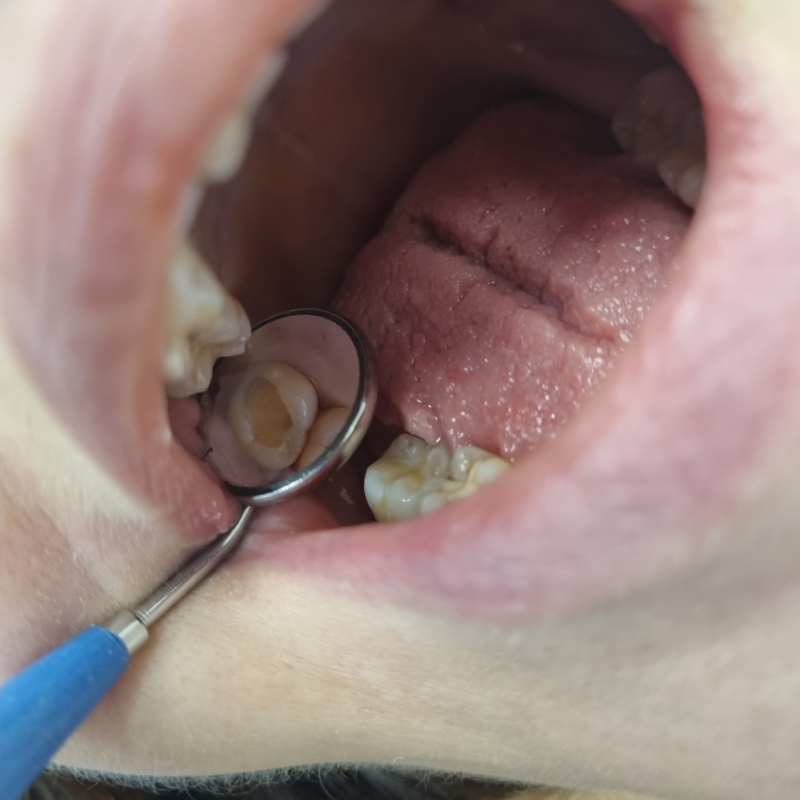

Лечение глубокого кариеса зубов 44 и 45 с использованием композита светового отверждения Estelite в «Стоматологии Комфорта»: фото до и послеСмотреть работуСрок лечения:90 минутСумма лечения:12 810 руб.